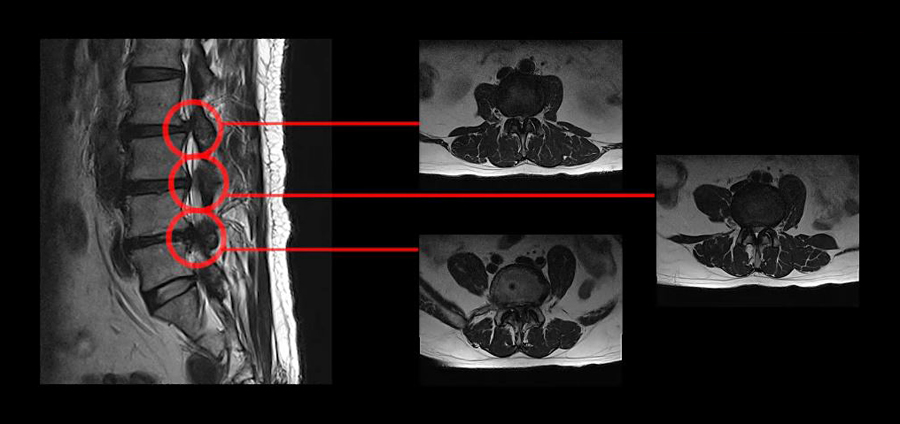

모커리에서 협착증 한방재활치료를 받은 환자의 MRI

위 MRI는 모커리한방병원 강남점에서 재활치료를 받으신, 척추관이 심하게 막힌 협착증 환자분의 MRI입니다. 이 환자분은 허리 세 마디에 심한 협착이 있으셔서 척추관 세 마디가 다 좁아져 있고, 아예 걷지도 못하고 허리도 못 펴는 상태였습니다. 대학병원에서는 수술도 어렵다고 할 정도였고, 다른 유명 척추병원에서는 3주에 걸쳐 3번 수술을 해야 한다고 했습니다. 이분이 만약 척추협착증원인 중 신경 눌림 때문에, 오로지 그 이유만으로 아픈 거였다면, 어떠한 비수술적 치료를 받아도 좋아지지 않아야 합니다. 더군다나 만약 이분이 비수술치료로 증상이 90% 이상 사라졌다면, 이게 어떻게 설명이 가능할까요? 이분의 치료후기를 아래 영상에서 꼭 확인하시길 바랍니다.